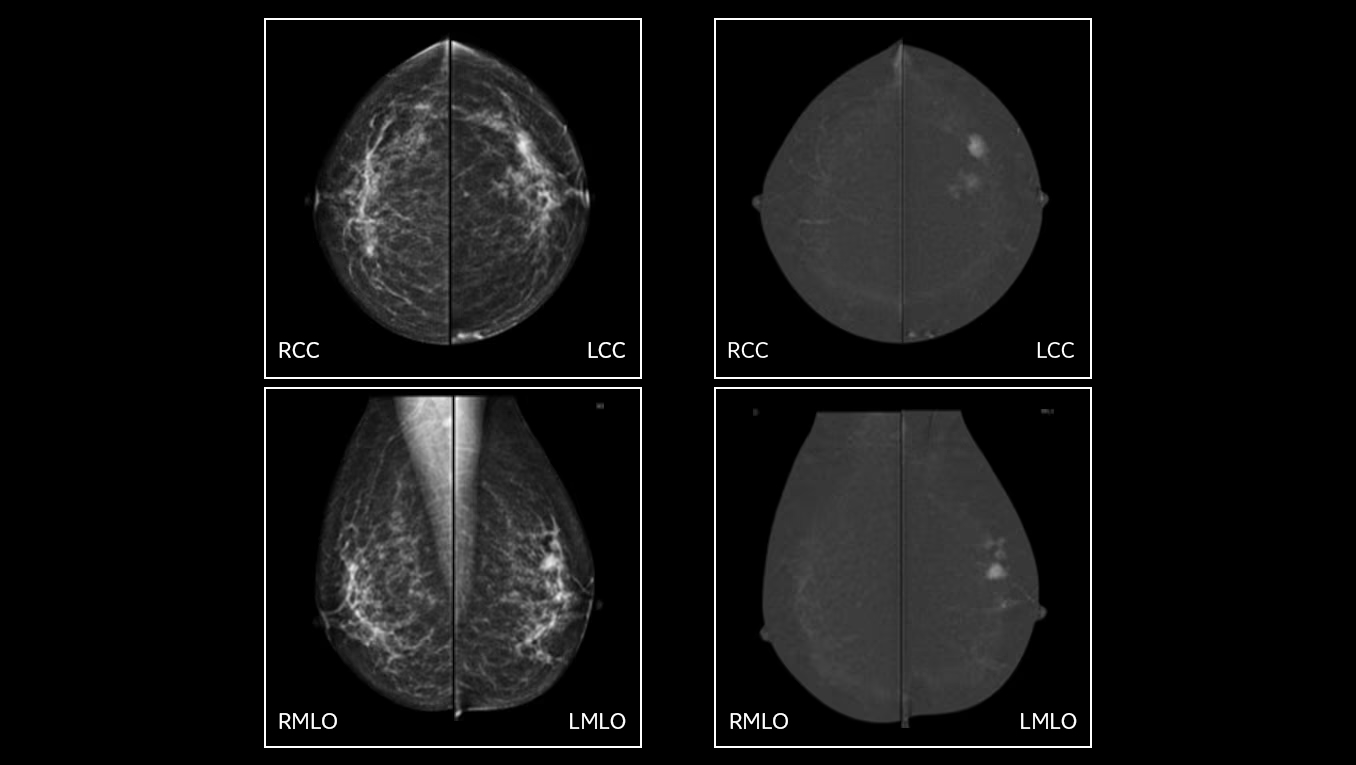

La combinazione tra immagine 2D sintetica e tomosintesi (DBT) consente di analizzare il seno “strato per strato”, offrendo una visione più chiara del tessuto mammario rispetto alle tecniche tradizionali.